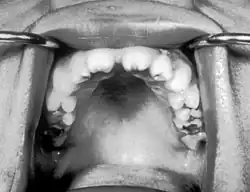

Malformações nos dentes associadas à sífilis congênita